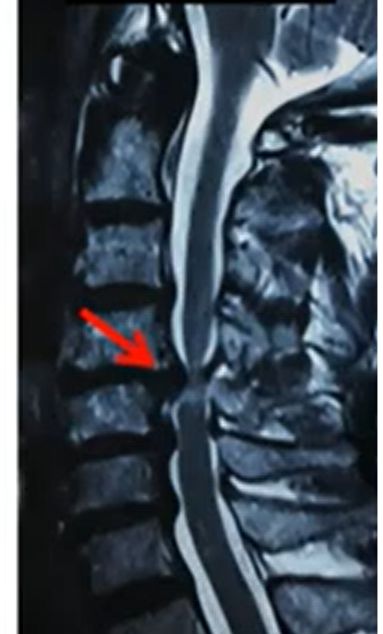

Surgery on the neck part of the spine to relieve pressure on the spinal cord or nerves.

- Patients with severe neck pain

- Pain spreading to arms

- Tingling or weakness in hands

- Walking imbalance due to spinal cord pressure